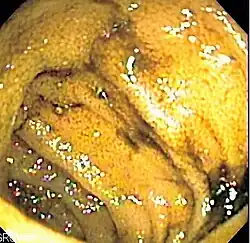

Endoscopic image of normal small bowel